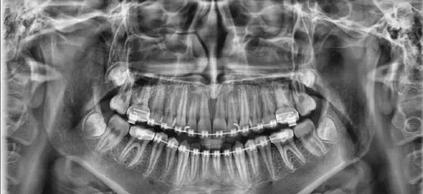

PaX-i 雙傳感器設備 |